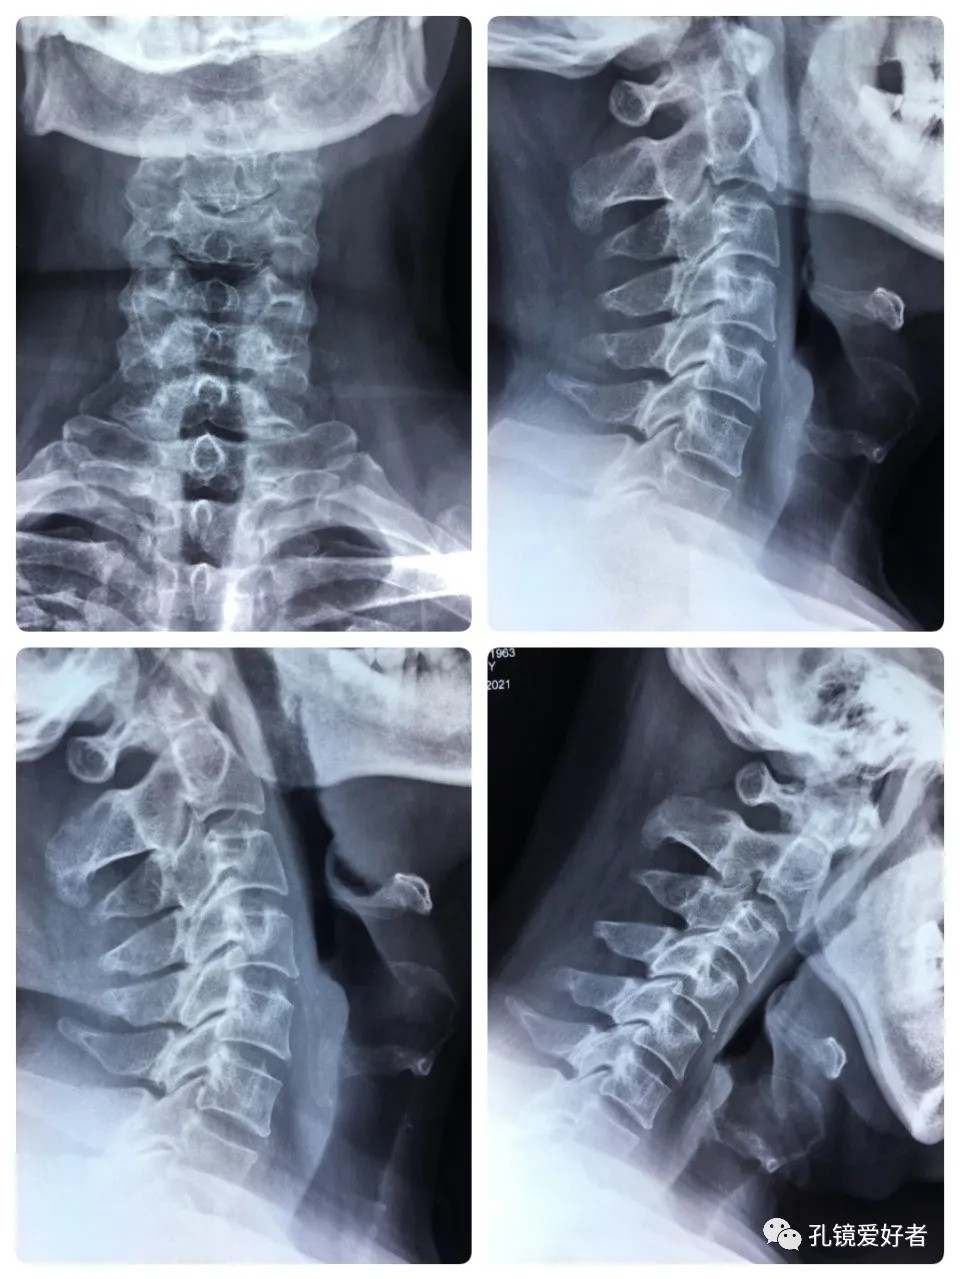

The patient's preoperative imaging data

The PA and lateral and flexion-extension position of cervical spine

The MRI shows that the cervical stenosis is on C3-4, C5-6 and C6-7. Considering the patient's clinical symptoms, C5-6 and C6-7 are the main affected segments. So it’s advised that the patient undergo posterior cervical open-door laminoplasty. According to the patient, he had visited many hospitals before and received similar proposals of diagnosis and treatment- posterior cervical open-door laminoplasty. The reason he came to our hospital was that he wanted his surgery could be performed in a minimally invasive way. After considerable preoperative discussion with my colleagues and the patient, we decided to perform the minimally invasive endoscopic decompression for C5-6 and C6-7 double-segment stenosis through posterior approach (with the Delta system).